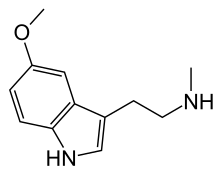

| 5-MeO-NMT | Plants | 5-OCH3 | H | CH3 | 5-methoxy-N-methyltryptamine | 2009-03-2 |